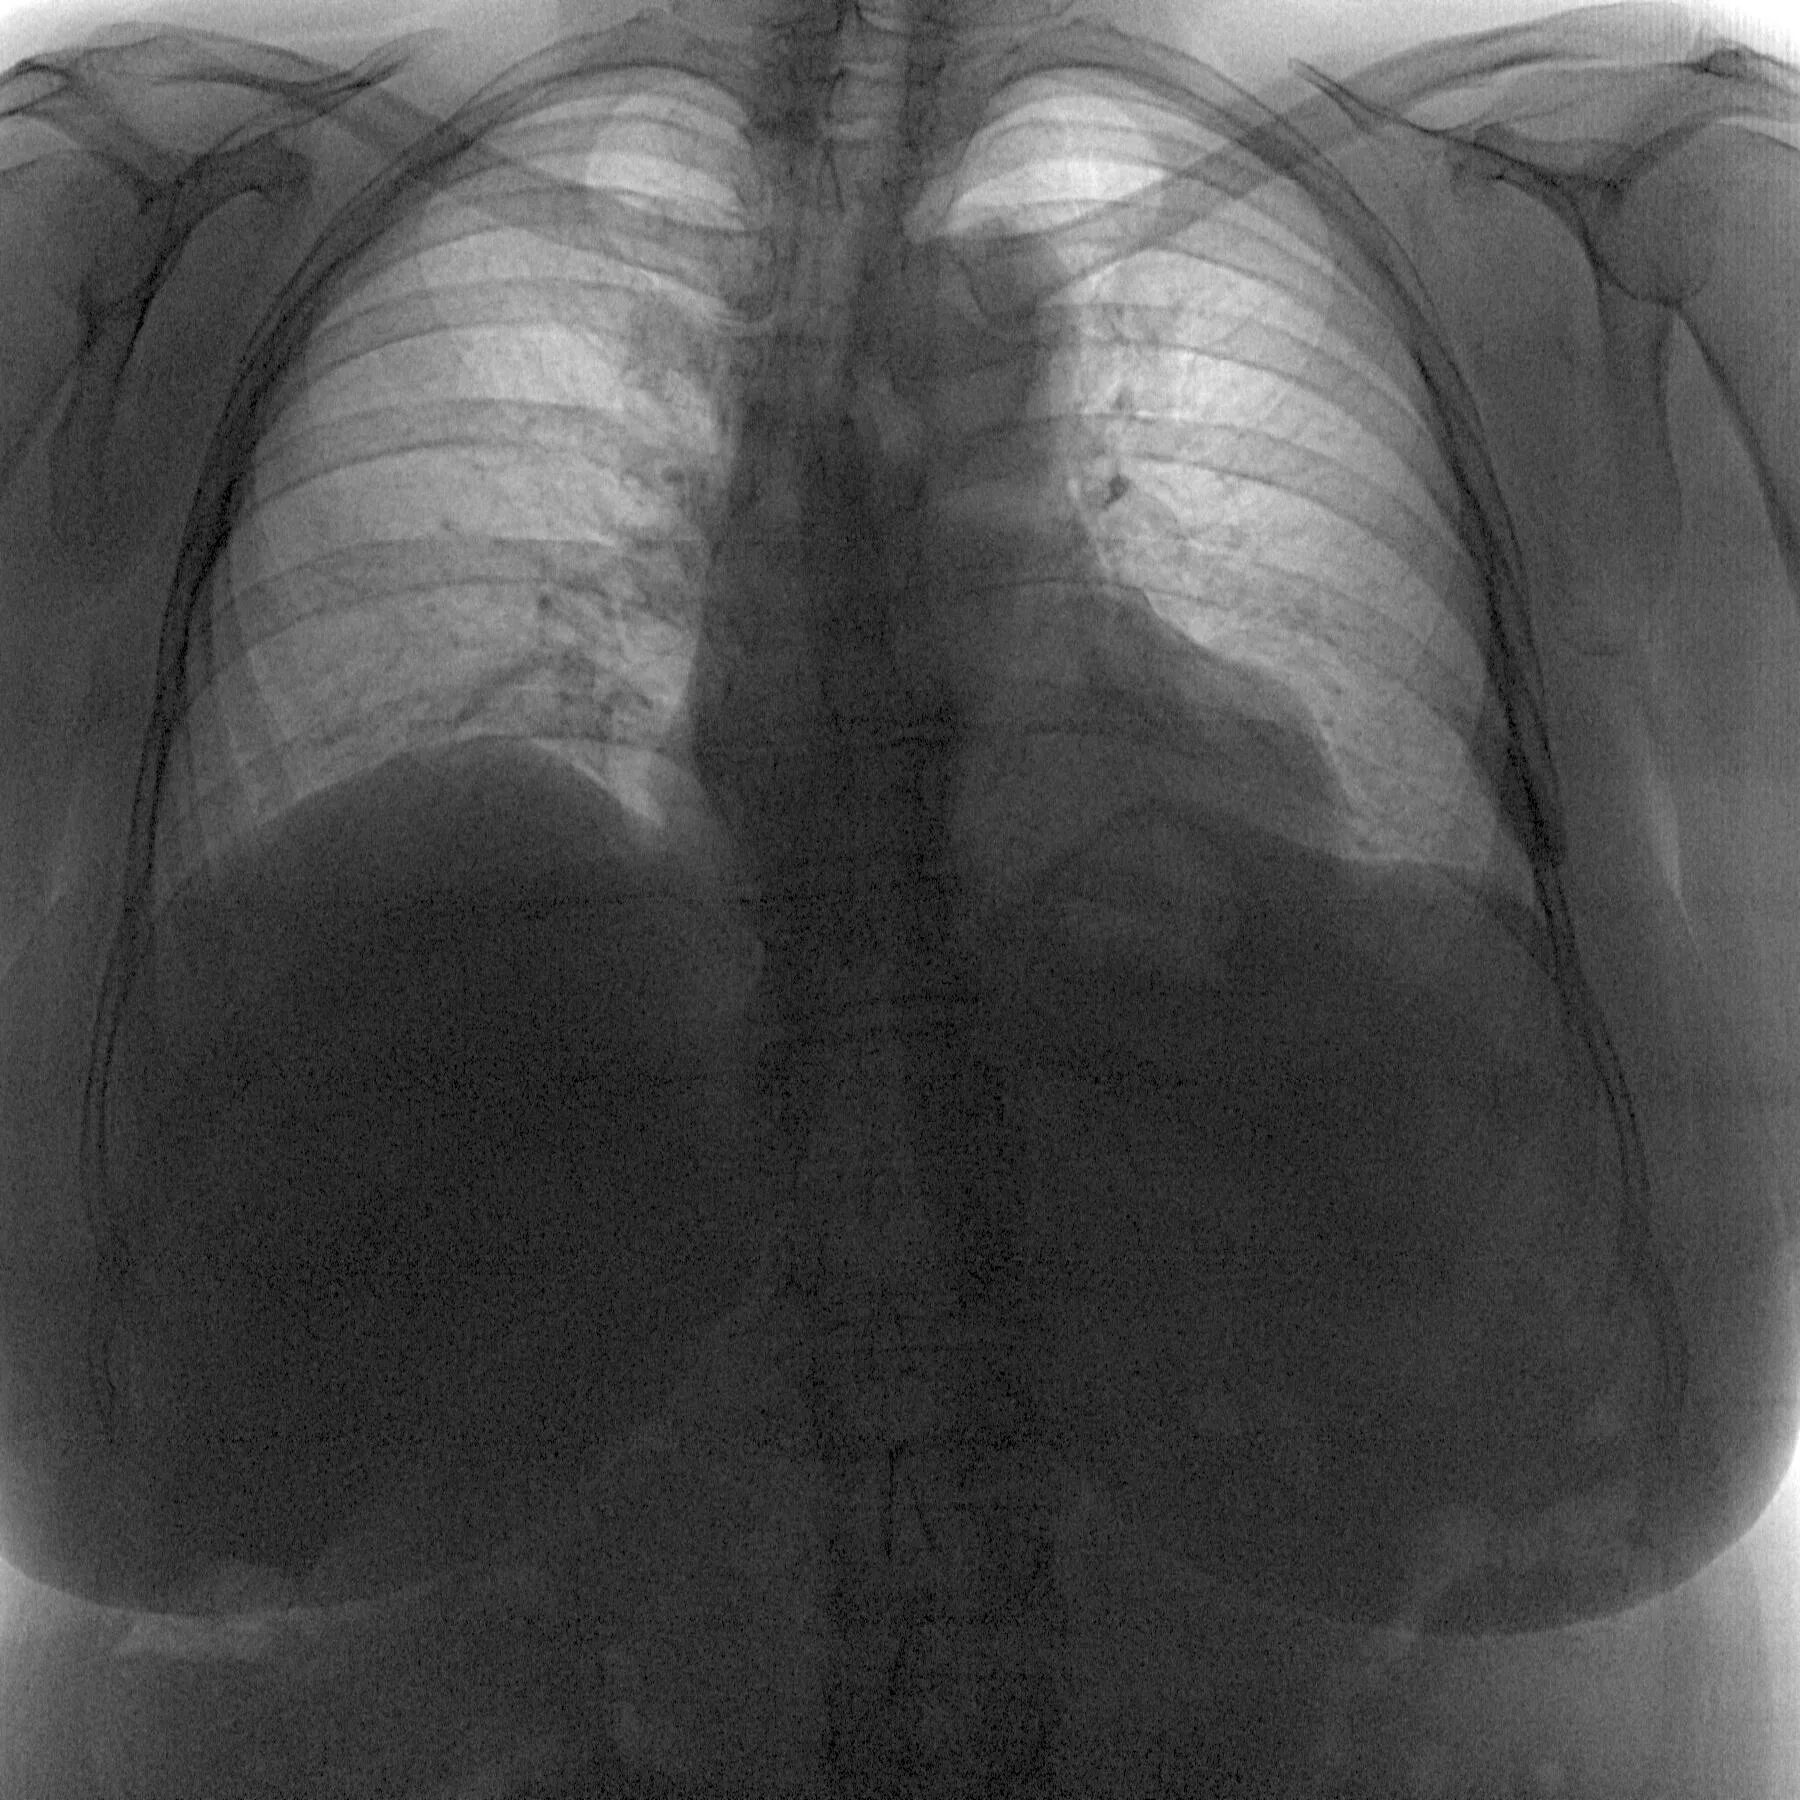

Ээд легких